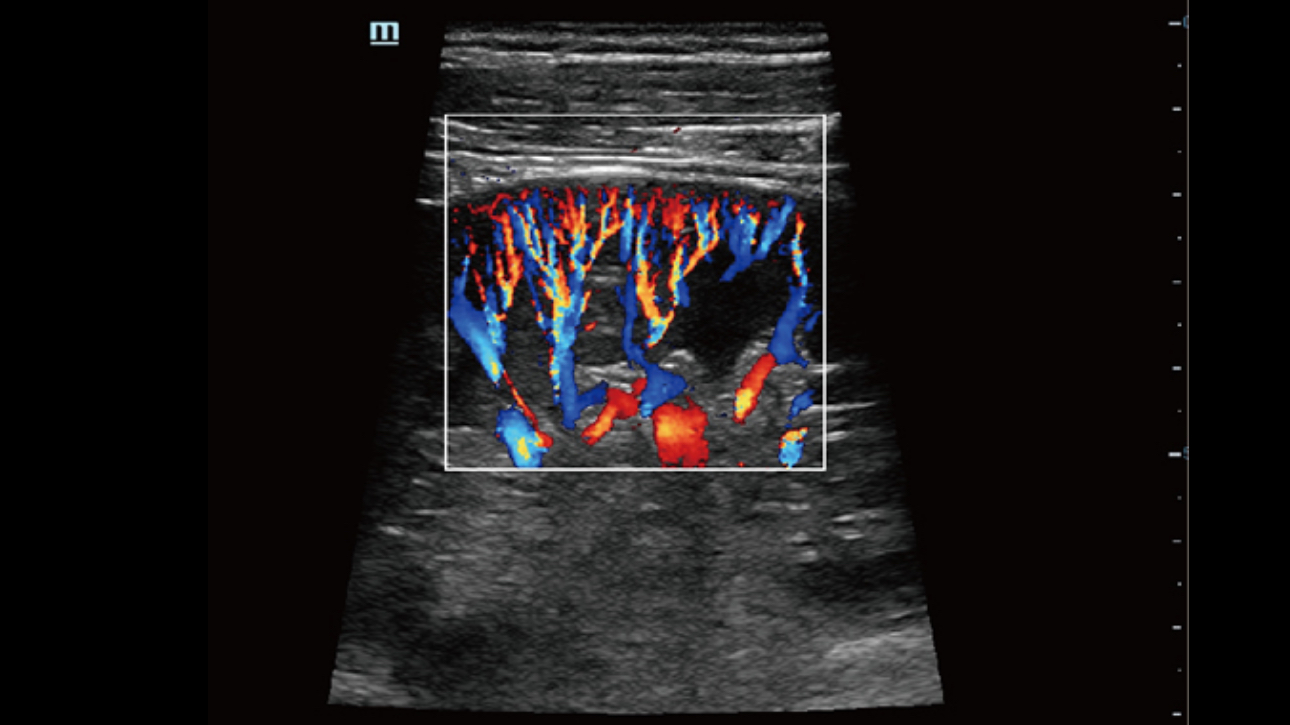

The channel data based ZST+ is an extraordinary innovation, representing an ultrasound evolution. Transforming ultrasound metrics from conventional beamforming to channel data based processing; ZST+ is able to deliver multiple imaging advances: Advanced Acoustic Acquisition, Dynamic Pixel Focusing, Sound Speed Compensation, Enhanced Channel Data Processing and Total Recall Imaging.

By transmitting and receiving a relatively smaller number of large zones, Advanced Acoustic Acquisition extracts more information from each acquisition, 10 times faster than a conventional line-by-line beamforming method.

Dynamic Pixel Focusing technology allows the Resona 6 to achieve extreme uniformity in pixel level throughout the whole field of view. Now there's no need to adjust the focal positions to achieve uniformity across patient exams.